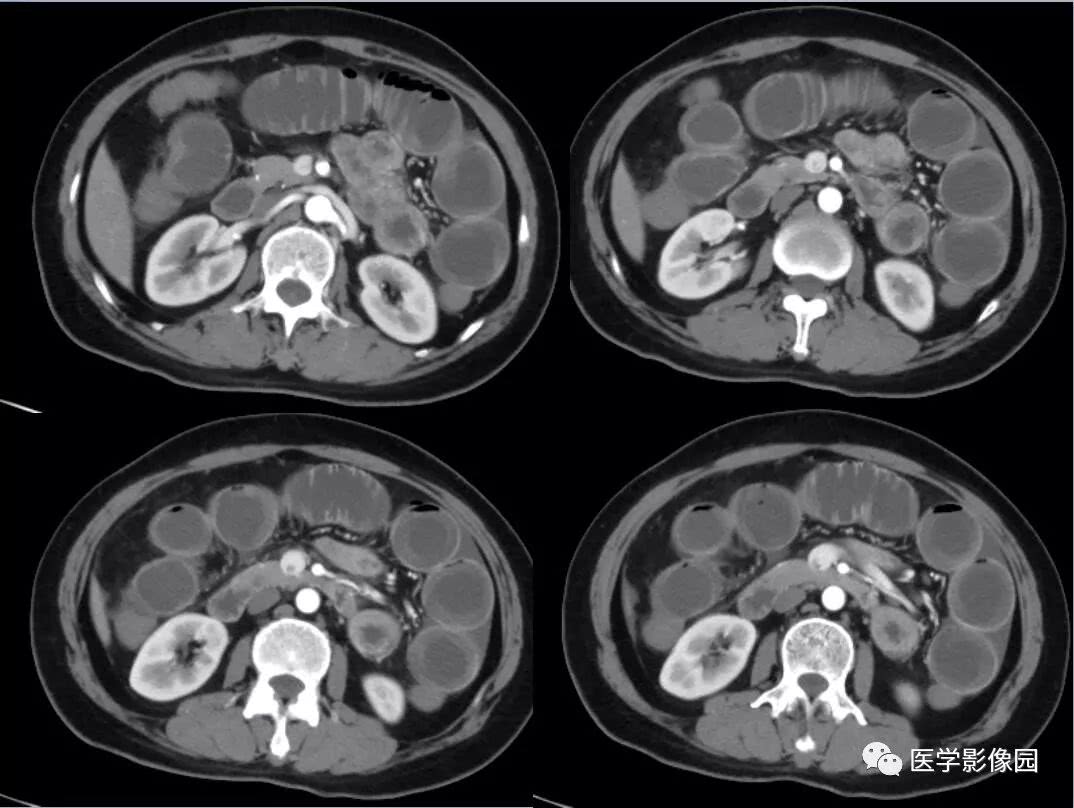

肠梗阻ct影像表现医学影像图

肠梗阻ct图片鉴赏